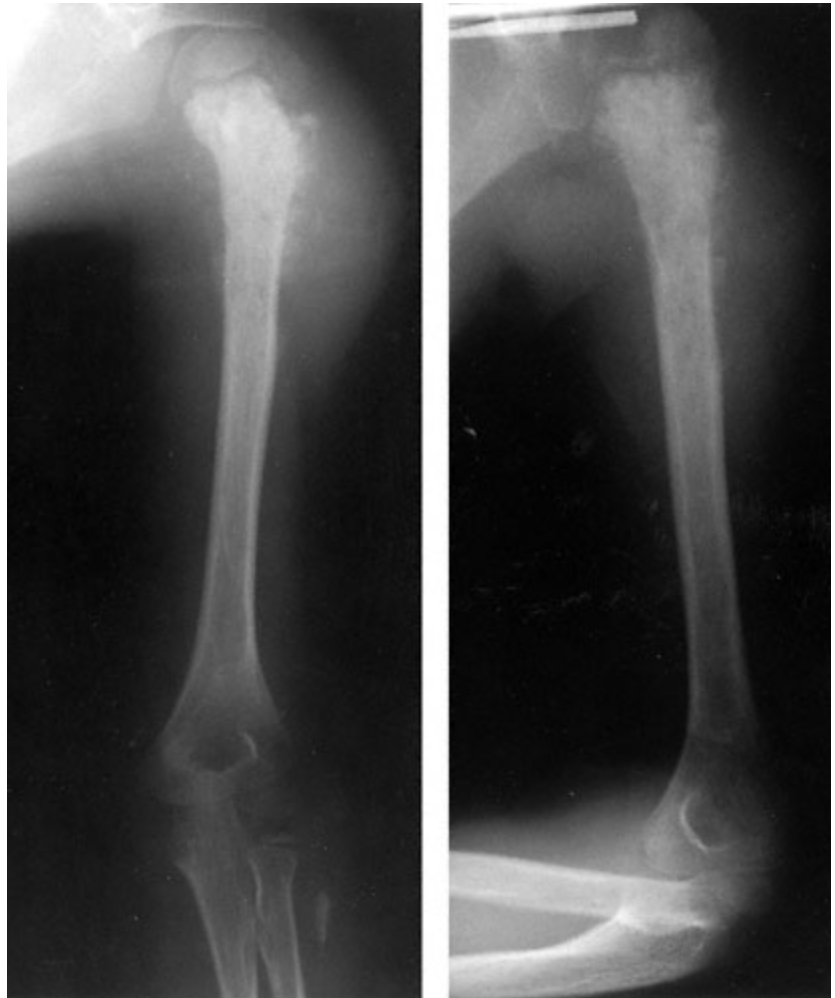

A previously healthy 7-year-old boy is brought to the physician because of a 3-week history of pain in his left shoulder and arm. He has difficulty raising his left arm over his head. The pain is worse with motion and at night; it often awakens him from sleep. Over-the-counter medications have not relieved the pain. There is no history of trauma. Examination of the left shoulder shows diffuse tenderness of the greater tuberosity involving the entire humoral head. Passive range of motion of the left shoulder is limited to 90 degrees of abduction and 70 degrees of forward flexion. Extension and flexion of the left wrist are full. Muscle strength and sensation are intact. Radial pulses are palpable bilaterally. X-rays of the left upper extremity are shown. Which of the following is the most appropriate next step in management?